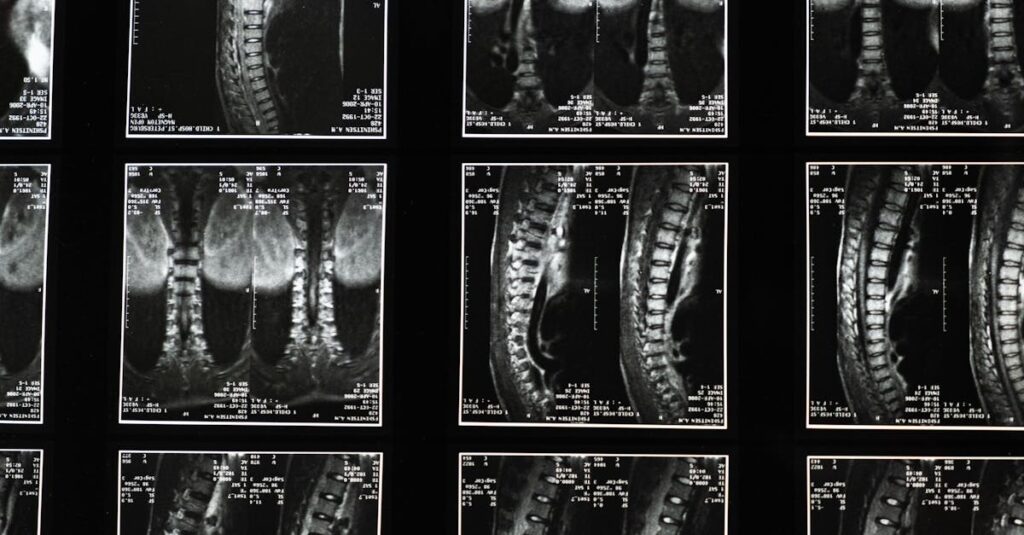

Quels examens permettent de diagnostiquer un pincement discal?

Une IRM ou une radiographie est souvent utilisée pour confirmer le diagnostic d’un pincement discal ou d’un disque écrasé.

Quels examens sont nécessaires avant de commencer un traitement de décompression pour un disque écrasé?

Une IRM ou une radiographie est souvent recommandée pour évaluer l’état de la colonne vertébrale.